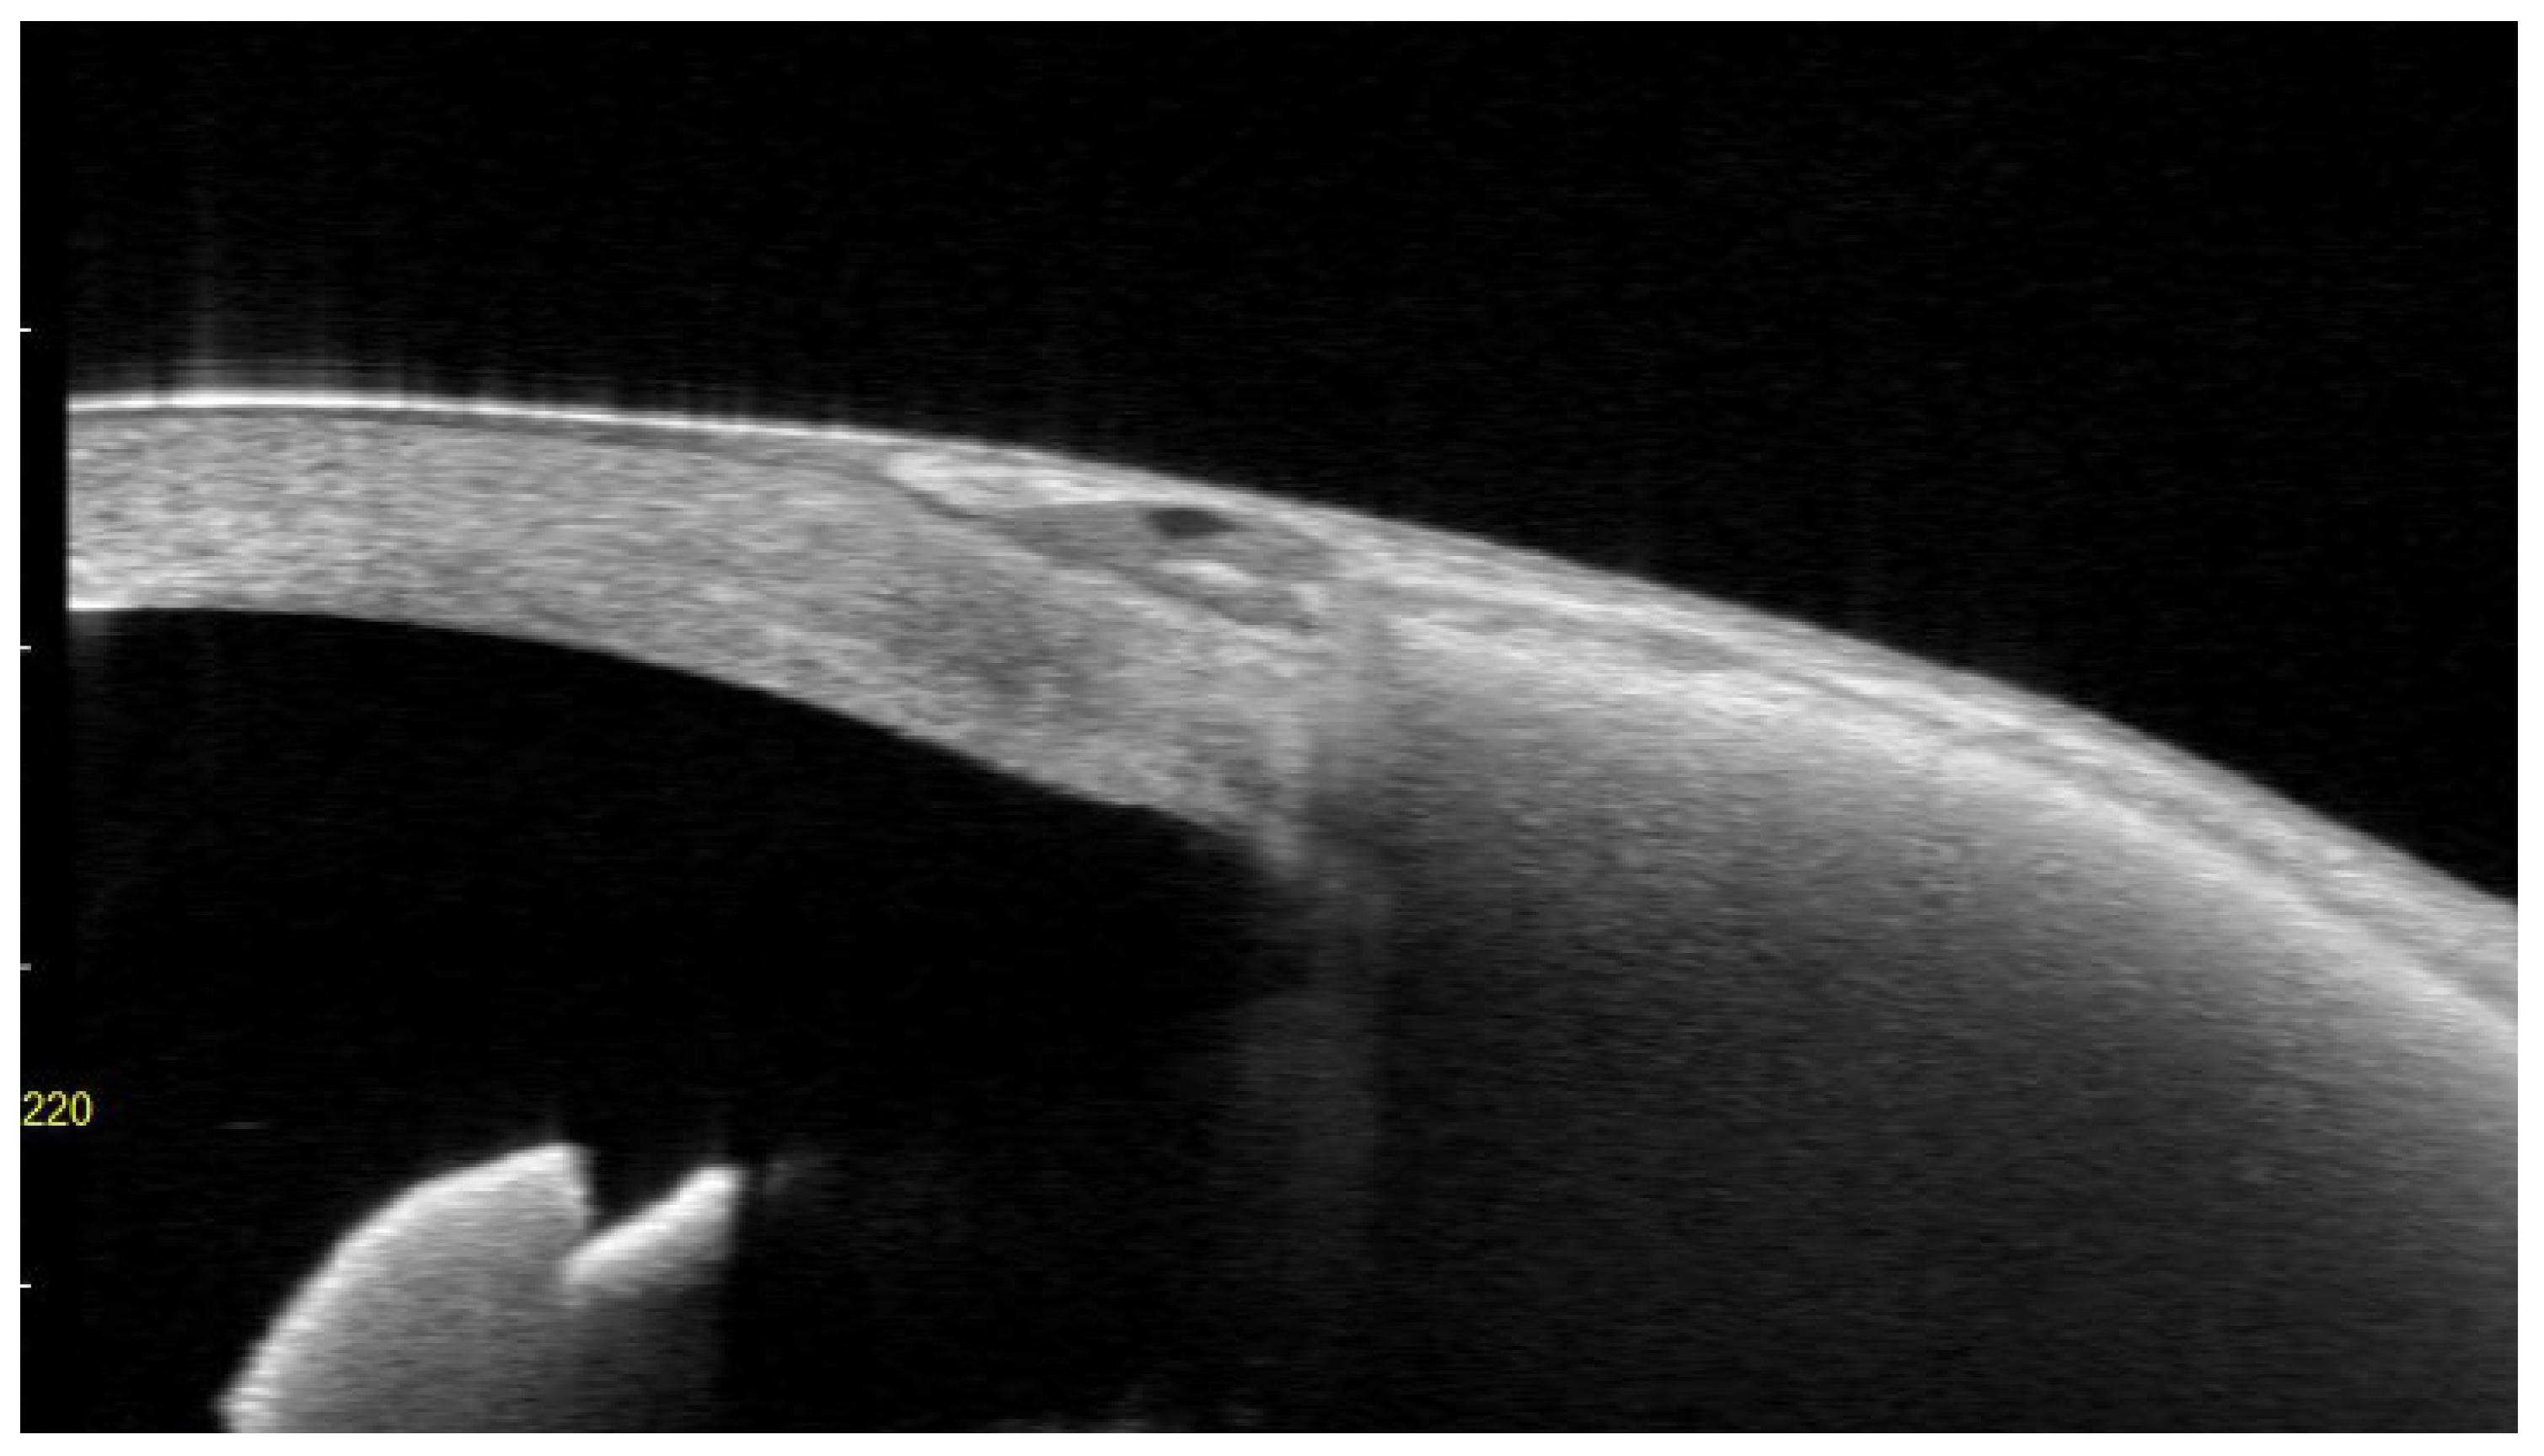

Figure 8. a,8b Anterior segment OCT findings in a case of conjunctival melting and subsequent EPP extrusion.

Preprints 201093 g008

Anterior segment OCT images obtained before extrusion at 6.7 months postoperatively (8a) and after extrusion at 8.9 months postoperatively (8b). Melting occurred in the central portion of the EPP, corresponding to the area of subsequent extrusion.

In contrast to mechanical conjunctival damage, a different mechanism may underly extrusion in certain EPP cases. In this series, two of the three eyes with extrusion exhibited conjunctival melting followed by extrusion, a pattern not observed in the 12 extruded cases using conventional biological patch grafts (Figures. 7 and 8). In these cases, there was no apparent elevation or prominence at the site of breakdown. Rather, the process began as a small dimple near the center of the patch approximately six months postoperatively and then progressed rapidly.